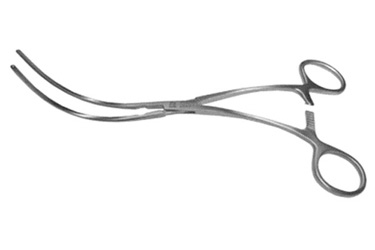

Catalog # : 353545 DEBAKEY AORTIC CLAMP

Curved, 3 7/8" (9.8cm) tip length, 2.4mm tip width, Curved shaft, 7 1/8" (18cm)